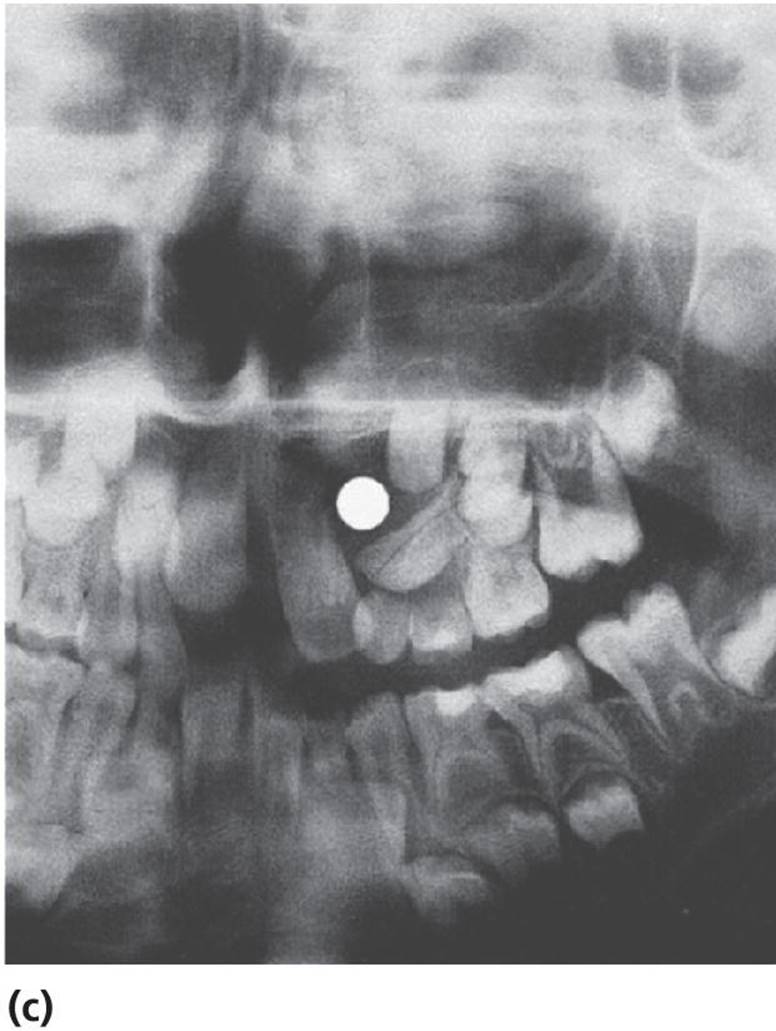

Cysts in the jaws, and especially large follicle cysts emerging from non‐erupted teeth, may displace teeth under development and disturb their eruption (Figure 15.29a–c). In children, it is important not to remove the cysts surgically as a first step procedure since this might damage a number of teeth and tooth germs. Instead, it is recommended in cases with large cysts that the cyst should be shrunk by use of rinsing with saline through an obturator introduced through the cyst wall (Figure 15.29d). In young individuals, the cyst will rapidly decrease and will be substituted by bone and often the dislocated teeth will spontaneously find their normal positions and eruption pathways.

Figure 15.29 (a) Extensive dentigerous (follicular) cyst in left maxilla emerging from a supernumerary tooth and displacing tooth germs and disturbing normal eruption in a 5‐year‐old girl. (b) Radiographic examination after 5 months revealed that the cyst had been reduced considerably and was now available for surgical removal without risk of disturbing the involved teeth. (c) After 4 months and surgical removal of supernumerary teeth and residual cyst tissues. (d) Obturator inserted to facilitate rinsing of the cyst. The obturator was removed after 6 weeks.